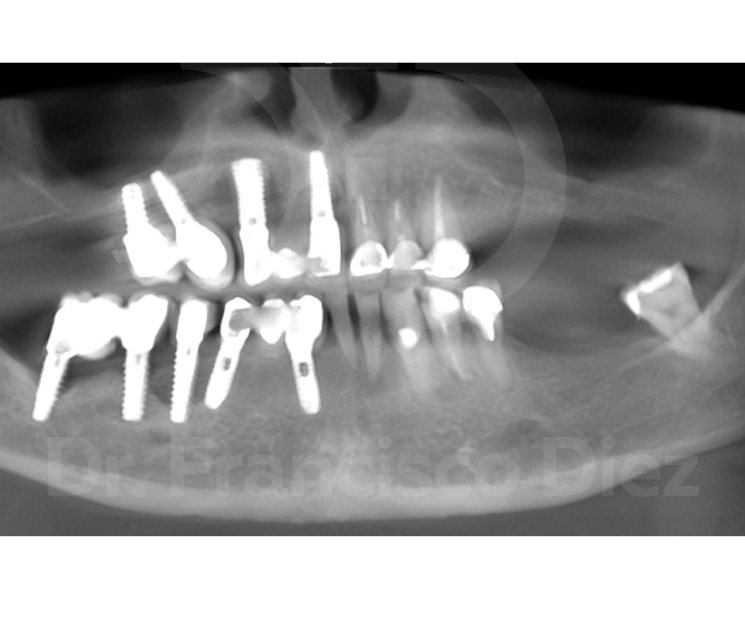

Veremos el caso clínico de un paciente de avanzada edad que llegó con estos problemas: no podía comer, ni sonreír, tras un mal diagnóstico y tratamiento erróneo.

Un factor crítico que agrava este escenario es la enfermedad periodontal. Las personas con predisposición a esta condición suelen terminar desarrollando periimplantitis cuando reciben implantes convencionales. El resultado es un empeoramiento muy significativo de su salud bucal. Intentar volver a colocar el mismo tipo de implante sería un gravísimo error, que conllevaría múltiples intervenciones, largas esperas y, a menudo, un resultado dudoso.

Frente a este panorama, existe una solución diferente: los implantes monofásicos corticobasales de carga inmediata. Su gran ventaja es que no requieren regenerar hueso. Trabajamos con el hueso basal, el que siempre está ahí, sin necesidad de incisiones complejas. En una sola intervención mínimamente invasiva favorecemos la curación y el crecimiento óseo. Y lo más importante: en 24 horas el paciente puede volver a comer cómodamente y a sonreír con confianza, sin inflamación, sin dolor y con un postoperatorio casi inexistente.